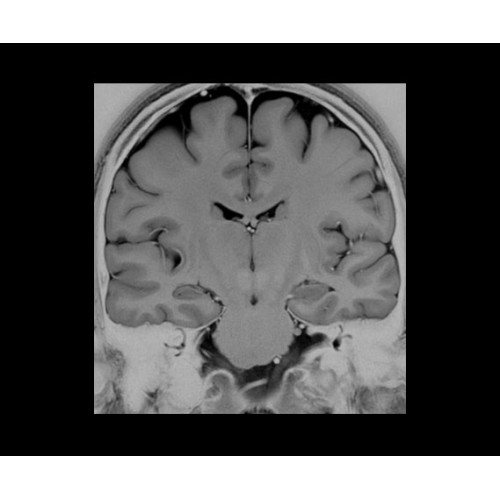

• NeuroWorks — универсальное решение для визуализации анатомии головного мозга, позвоночника, сосудов и периферических нервов с четкой дифференциацией тканей.

• 48-канальная катушка TDI для головы, входящая в базовую комплектацию SIGNA Architect, обеспечивает феноменальную производительность с учетом особенностей каждого пациента. Благодаря гибкому и универсальному дизайну, высокому соотношению сигнал/шум и передовым технологиям визуализации, таким как HyperWorks, учитываются потребности подавляющего большинства пациентов.

SIGNA Architect 3.0T — это новейший МРТ аппарат компании GE, который предлагает высочайший уровень производительности — в системе 128 приемных каналов, 48 канальная катушка головы, полный спектр клинических возможностей. Высокий уровень комфорта пациента обеспечивают такие особенности как отсоединяемый стол, положение пациента «ногами вперед» для всех видов исследований, SilentWorks — бесшумное и MAGIC — быстрое сканирование.